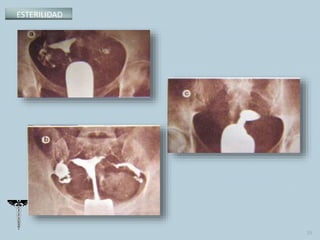

•Histerosalpingografía.

 Histerosalpingografía.